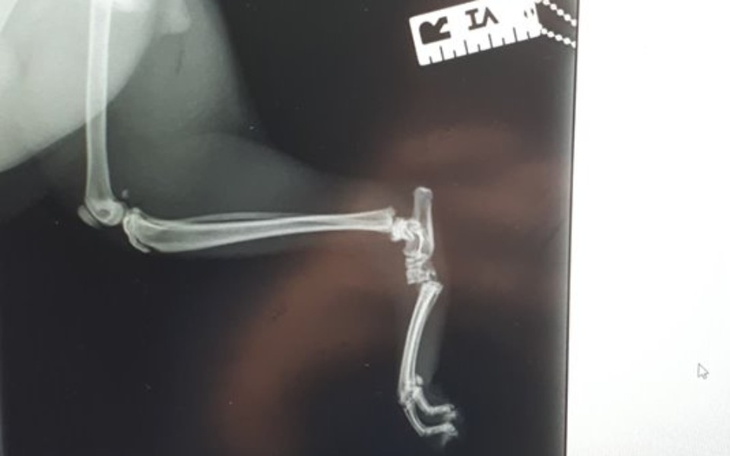

Witam, bardzo proszę o pomoc w zebraniu pieniędzy na operacje mojego kota Wafla. W niefortunnym wypadku w domu uszkodził sobie stopę, przez co bardzo słabo chodzi, a operacja jest jedyną nadzieją na wrócenie do sprawności. Przez rozległe złamanie widoczne na zdjęciu nie jest w stanie nawet poprawnie skorzystać z kuwety. Sprawia mu to ogromny ból i bardzo cierpi. Jest to młody 11 miesięczny kocur, pełen wigoru i sił. Niestety kwota, która jest potrzebna na zrealizowanie operacji jest dla nas ogromna. Cała operacja to koszt 2,5 tysiąca złotych. Na ten moment udało nam się zebrać 500 zł lecz to nawet nie jest połowa. Bardzo proszę o pomoc, mamy mało czasu, operacja powinna odbyć się w terminie do 2 tygodni. Kot jest dla nas jak członek rodziny i chce by znów mógł normalnie funkcjonować.